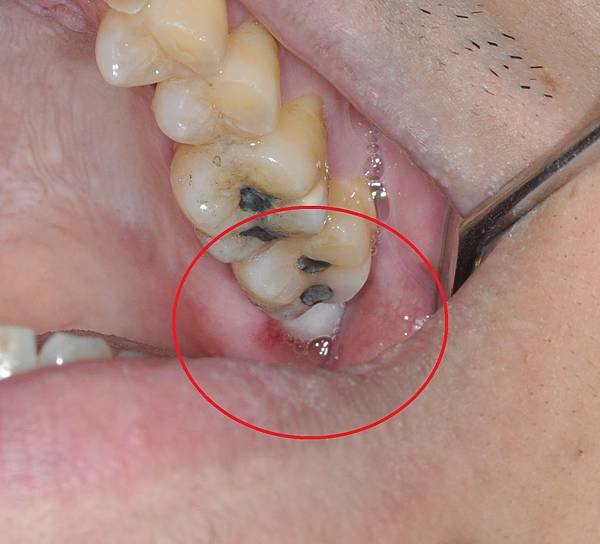

拔牙後的傷口是一個深洞

2-3天內就穩定下來不再滲血

但完全長好肉需要3-4週

膠原蛋白敷料就是在拔牙後

塞到傷口裡填滿這個空間

除了減少傷口腫漲程度比較舒服外

也比較不會塞東西